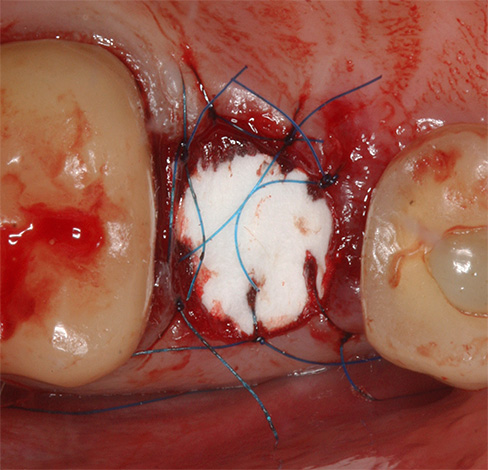

- De acordo com o depoimento, as costuras são sobrepostas no buraco, um guardanapo de gaze é instalado com ou sem a droga;

- Recomendações para o tratamento de feridas são fornecidas e são prescritos enxaguatórios e medicamentos anti-sépticos para aplicação tópica na forma de géis ou pomadas.

A colocação de qualquer droga no próprio buraco é um método desatualizado, mas, para instituições orçamentárias, é atualmente um dos mais eficazes no tratamento da alveolite, embora não exista certas desvantagens.